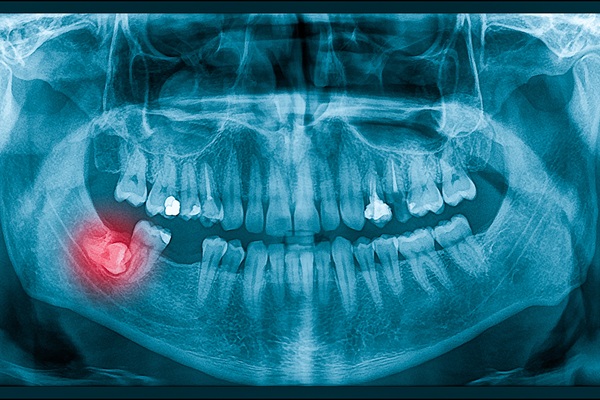

However, if there is no adequate space for the wisdom teeth to emerge or if the teeth are coming through in the wrong position, they may become impacted (or trapped in the jaw or under the gums). This may cause cysts, damage to neighboring teeth, gum disease, infection, pain, tooth, decay, and tumors. A dentist needs to monitor the patient's wisdom teeth and determine the best course of action.